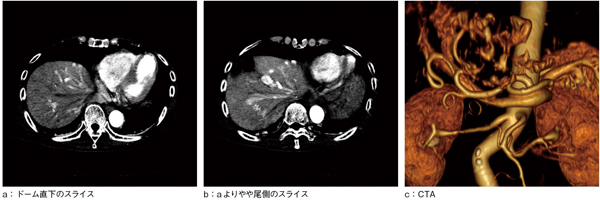

症例は,60歳代,女性,繰り返す意識障害による転倒外傷あり。採血および造影CTにて,肝内門脈体循環短絡(intrahepatic portosystemic venous shunt:IHPSVS)による肝性脳症が疑われた。血管内治療の適応について,当院に紹介された。前医の造影CTにて,血流異常が多発していることは明らかだが,動静脈短絡と門脈体静脈短絡との判別は困難で,治療適応の可否は判断できなかった(図1)。

図1 血管塞栓術前の造影CT動脈相

肝動脈枝の拡張,門脈枝の拡張,肝静脈の造影増強効果を認める。

CTAでも血行動態解明は困難である。